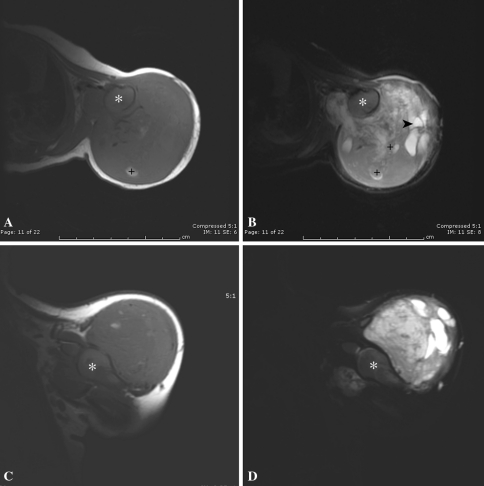

Fig. 4A–D.

(A) An axial T1-weighted image shows a large soft tissue mass involving all quadrants of the arm, without bony invasion, and an (B) axial fat-saturated T2-weighted image shows heterogeneous enhancement with gadolinium. (C) A coronal T-1 weighted image shows the soft tissue mass involving all quadrants of the arm, and the (D) fat-saturated T2-weighted image shows heterogeneous enhancement with gadolinium. The lateral aspect of the mass contains a substantial cystic component; a fluid-fluid level (B, arrowhead) is seen. Deep tubular structures of variable signal intensity, labeled with black plus-signs (+) may represent dilated, low-flow venous components. The humeral head is annotated with a white asterisk (*).

Plain radiographs (Fig. 3) showed a large soft tissue mass causing secondary humerus remodeling and slight valgus angulation but with no definitive bone invasion or scalloping. MRI showed this large lesion (Fig. 4) better. It was a well-circumscribed, discrete, heterogeneous mass, relatively isointense to muscle on T1-weighted imaging, with variable areas of moderately increased signal on T2-weighted images. In the areas of solid tumor, cystic fluid-fluid levels and tubular structures with varying signal intensity also were evident. The mass extended medially into the axilla and from the superolateral aspect of the arm to the distal third of the triceps compartment. There was no direct invasion of the bone or periosteum.